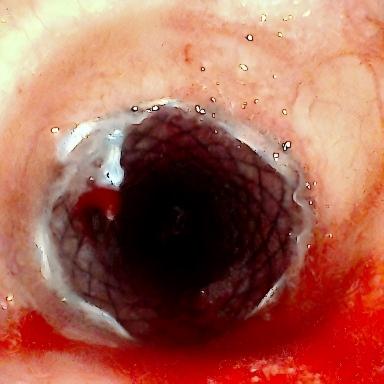

方案确定后,ICU团队何智辉、邢伟、邓龙天为患者建立体外生命通道;呼吸介入团队孟婕、杨红辉、刘建明、邹丽君、贺一峻等通过球囊对狭窄部位进行预扩张,随后在距隆突仅1.6cm的低位气道精准植入支架。支架贴合良好,气道顺利开通,全程操作约1.5小时。患者当晚撤离ECMO,次日从ICU转回普通病房。后续肺泡灌洗液检测显示,患者大气道狭窄的原因为气管结核导致的瘢痕性狭窄。